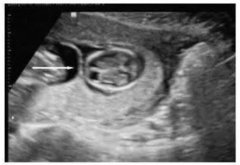

孕早期做b超對胎兒有影響嗎?孕早期B超檢查內容

當今的家庭,孩子都是很重要的,只要知道懷孕了,都會擔心這擔心那,就像現在有不少的準媽媽擔心孕早期的B超檢查會影響胚胎的發育,自己認為照B超...